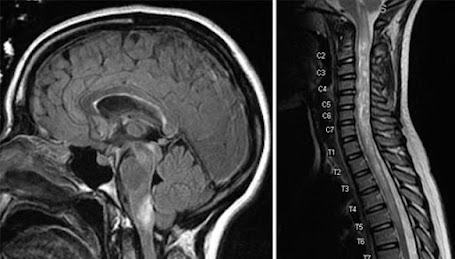

Image: MRI-Of Neuromyelitis Optica www.health.uconn.edu

Neuromyelitis Optica (NMO) is a disorder of the central nervous system it primarily affects the nerves of the eye (optic neuritis) and the spinal cord (myelitis), but can also attack the brain. NMO It is also known as the Devic disease. It occurs when the body's immune system reacts against its own cells in the central nervous system.

1. Testing for NMO and MS May include an MRI (magnetic resonance imaging) skin tissue inflammation of the spinal cord - The difference is NMO scans show long segments of inflammation and with MS the findings tend to show short segments of inflammation.